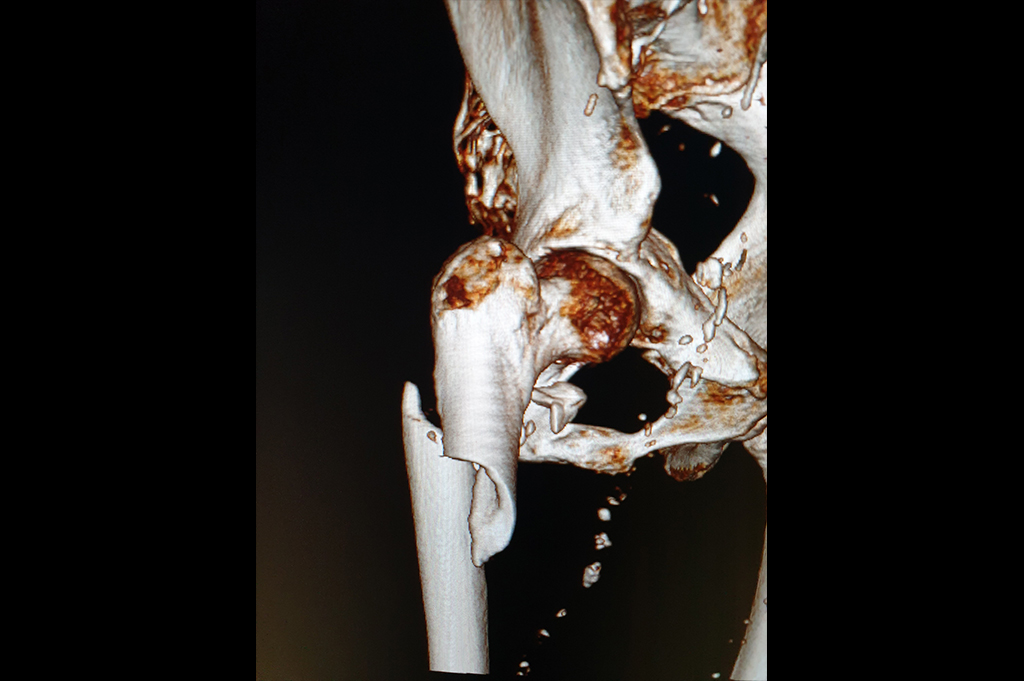

Neck Femur Fracture

Subtrochanteric Fracture